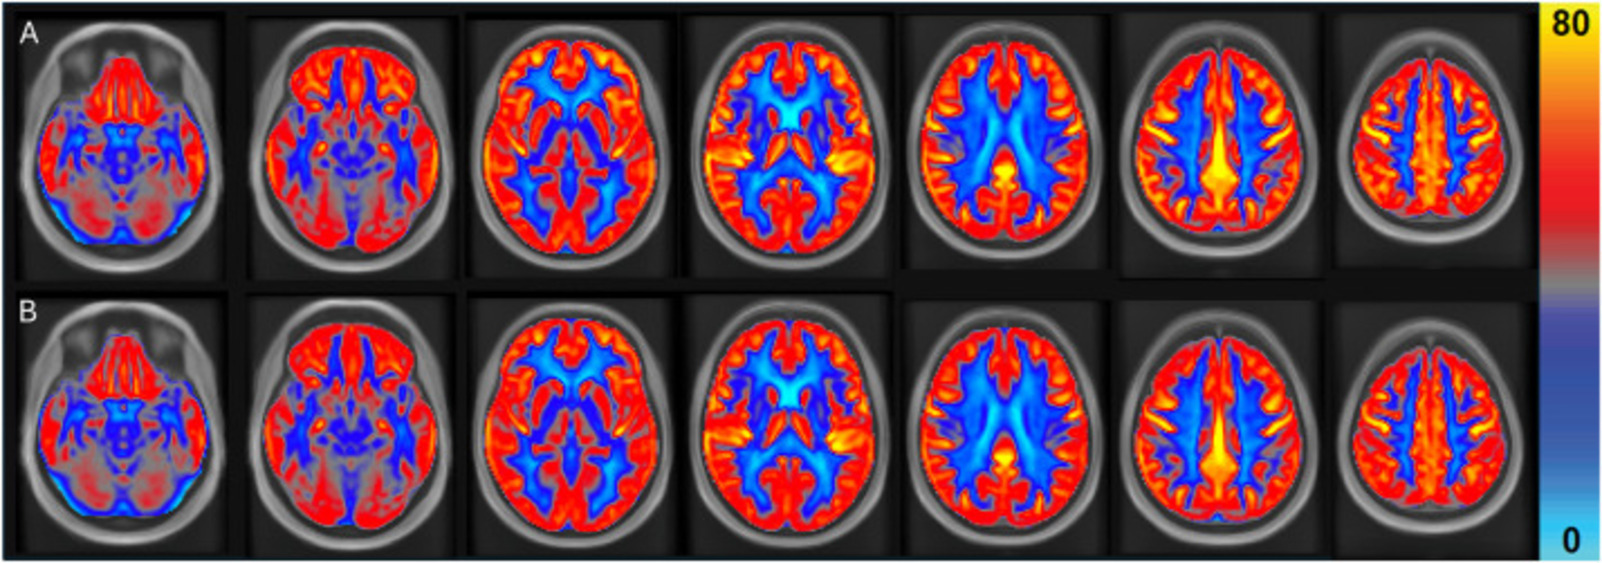

На первой карте видно состояние мозговых сосудов после 16 недель ежедневного употребления арахиса. На второй — тот же показатель, но в контрольный период, когда участники не ели арахис и избегали орехов.

Цвета на снимках отражают уровень кровотока: чем ярче оттенок, тем больше крови поступает к мозговой ткани. Исследователи наложили снимки всех 31 участника друг на друга и привели их к единому стандарту, принятому в нейровизуализации, чтобы сравнение было максимально точным.

После 16 недель с арахисом общий кровоток в мозге вырос в среднем на 3,6 %. Серое вещество получало на 4,5 % больше крови. Особенно заметны были сдвиги в лобных и височных долях — на 6,6 и 4,9 % соответственно. Эти области отвечают за память, речь и сложные когнитивные задачи.